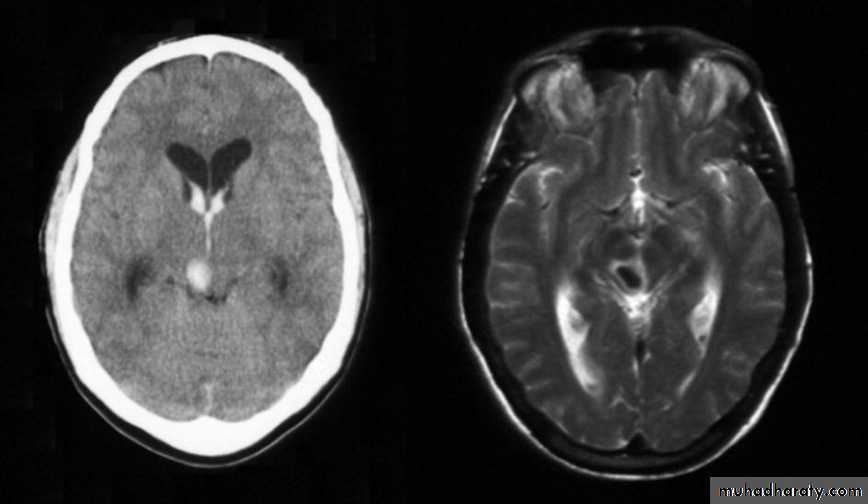

C-Intracranial hemmorhage (I.C.H.)

I.C.H.

2-CT-Scan

3-MRI